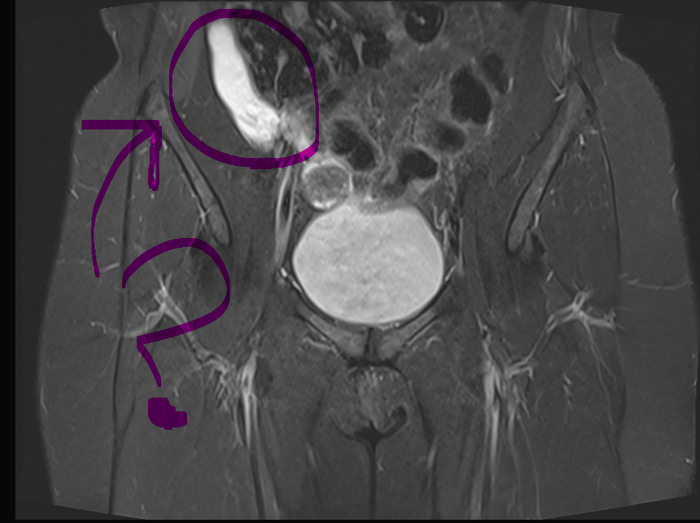

Подсказка - вы смотрите на человека, будто он перед вами. Большая круглая штука посередине - мочевой пузырь. Чуть выше черно-серая колбаска - кишки.

На месте! Это туго набитый слизью аппендикс, 7х3 см. Да ещё и сияет.

Да тут даже последний кучер с Бейкер-стрит скажет, что получилось, без привлечения Холмса, Ватсона и Хадсон. МР-диагност откровенно положил болт на клинические данные ("боль в правой подвздошной области" - огромный намек, что надо там тщательно всё излазить!). А хирурги доверились заключению своего диагноста и не стали пересматривать диск. Типа "ну ничего не нашли, и ладно с ней, может, просто истеричка".